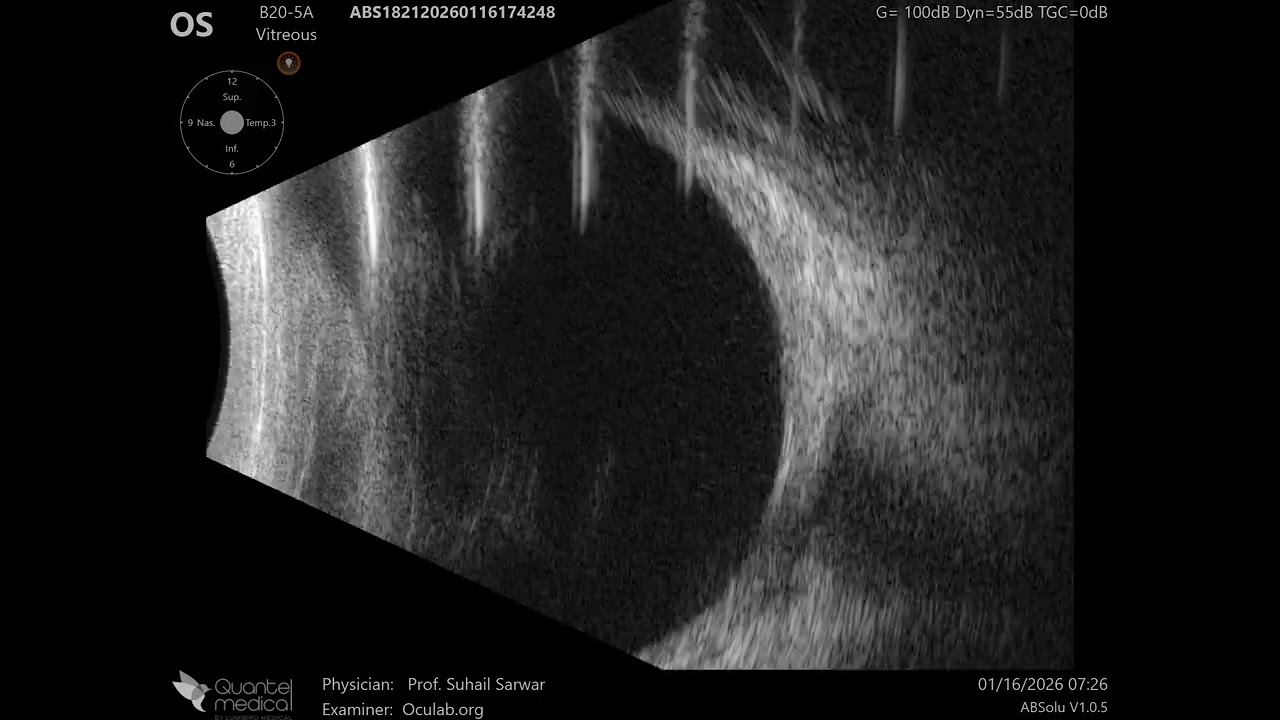

20 MHz Annular Ophthalmic Ultrasound ABSolu, Fungal orbital cellulitis , 36925

Hertel's Exophthalmometry RIGHT eye = 20.0 mm, LEFT eye = 21.0 mm.

B-scan LEFT eye / orbit shows (fungal?) orbital cellulitis prominent in superior anterior extraconal space with cellulitis in intraconal spaces as well. Marked thickening of medial rectus is noted.

Condition status quo.